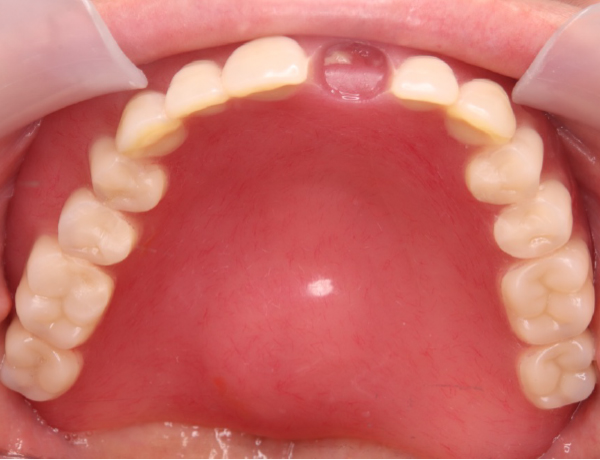

上あご

赤丸の部分にこれでもかってくらい大きな骨の隆起があります。噛む力がかなり強そうです。

1. 噛む力が非常に強い お口の中には骨隆起が認められました。赤丸で示している部分が、口蓋隆起と呼ばれる骨の盛り上がりです。このような骨隆起がある場合、噛む力が一点に集中しやすく、入れ歯に通常以上の負担がかかります。